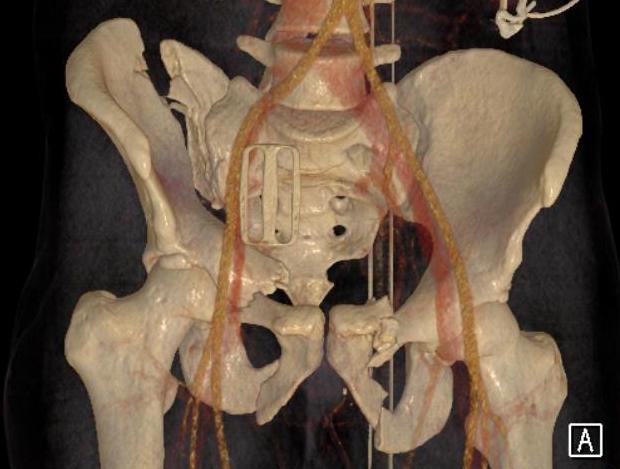

LC-1: pubic rami fracture with sacral fracture

Posterior fixation

Percutaneous sacroiliac screws